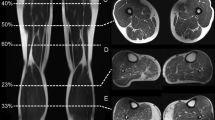

IN order to test for functional competence in thin pieces of isolated tissue containing muscular elements, such as the skin of the rat (which contains smooth muscle and a sheet of skeletal muscle known as the panniculus carnosus)', a bath was devised in which the muscles could be excited directly or indirectly by transmural stimulation1. The response of the stimulated muscle provided a measure of functional competence in the surviving tissue. This bath and also our method of recording the pressure changes developed in it are described here.